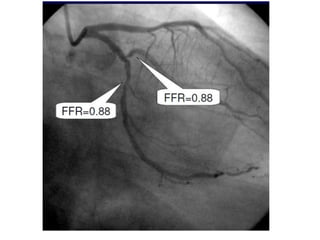

FFR

Definition

• It is ratio of driving pressure of

microcirculation flow distal to stenosis to

driving pressure proximal to stenosis in a

maximally dilated microvascular resistance

vessels (R2).

• FFR = Pd/Pa0

Fractional flow reserve

• Equivocal or intermediate lesions , and in the absence of

demonstrated ischaemia, decision making based on

angiography alone is challenging.

• FFR has been extensively described and validated as a

technique capable of identifying functionally significant lesions

• FFR value below the threshold value of 0.75 corresponds to

inducible ischaemia

• Studies have shown that a strategy of revascularization based

on FFR results in this context is acceptable.